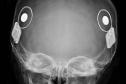

30/03/2026-Paraná assume liderança nacional em implantes de correção auditiva pelo SUS

Paraná assume liderança nacional em implantes de correção auditiva pelo SUS